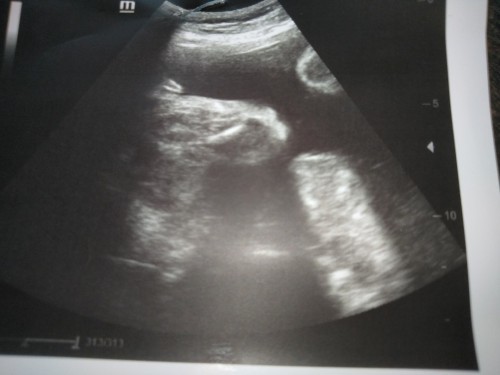

ลูกสาวบ้านนี้

Post reply image